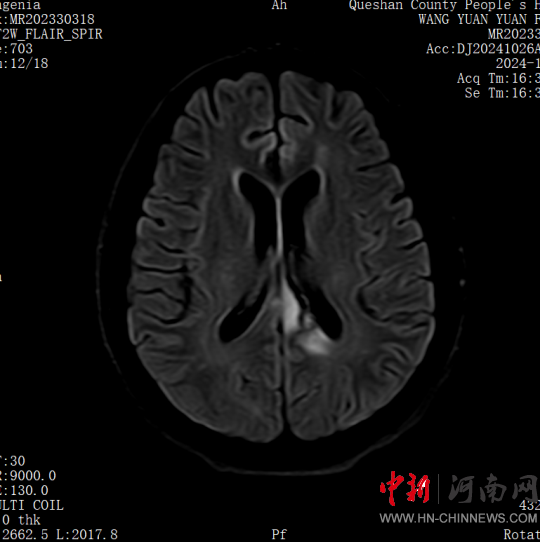

患者,女,32歲,車(chē)禍傷,到達(dá)確山縣人民醫(yī)院急診科創(chuàng)傷中心救治時(shí)血壓80/45mmHg,心率115次/分,處于昏迷、休克狀態(tài),病情危重。急診科迅速啟動(dòng)創(chuàng)傷中心急救綠色通道,醫(yī)護(hù)人員立即展開(kāi)搶救,積極抗休克治療的同時(shí),聯(lián)系神經(jīng)外科、胸外科、急診重癥監(jiān)護(hù)室緊急會(huì)診,同時(shí)快速CT、床旁FAST檢查明確診斷。通過(guò)一系列急救措施,患者的休克狀態(tài)稍微好轉(zhuǎn),經(jīng)多學(xué)科會(huì)診后明確診斷為:多處損傷并失血性休克、彌漫性軸索損傷、蛛網(wǎng)膜下腔出血、腦挫傷、股骨及脛腓骨粉碎性骨折、多發(fā)肋骨骨折并肺挫傷、腰椎骨折。ISS評(píng)分高達(dá)50分,死亡率極高,患者病情危重,立即送入急診重癥監(jiān)護(hù)室進(jìn)行高級(jí)生命支持治療。